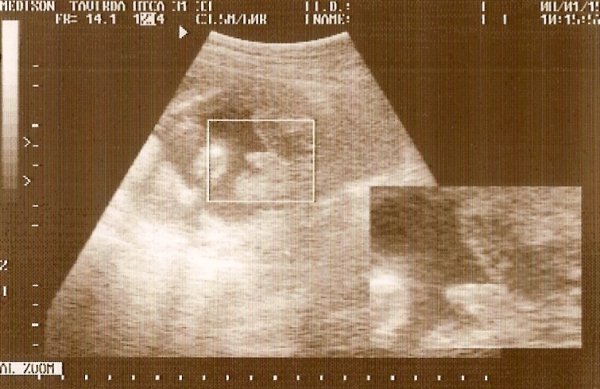

Örülök, hogy minden rendben van a kicsivel. Szép súlya van már, pihizz sokat a méhszáj miatt, aztán pár hét múlva már akár jöhet is.